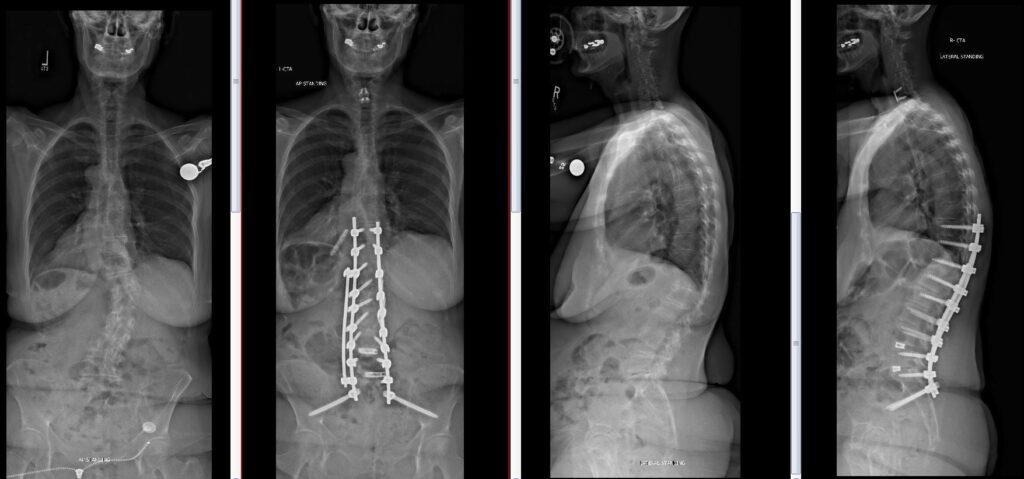

Deformity Surgery